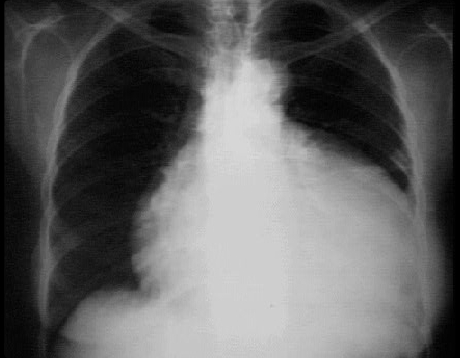

This chest X ray shows a pericardial effusion.

This PA view shows a markedly enlarged cardiac silhouette producing a water bottle appearance. Note the neck region of the water bottle formed by the normal aortic shadow.

Note also the normal pulmonary vascularity of the lung fields, an important hint that this enlargement of the cardiac shadow does not reflect underlying chamber enlargement.